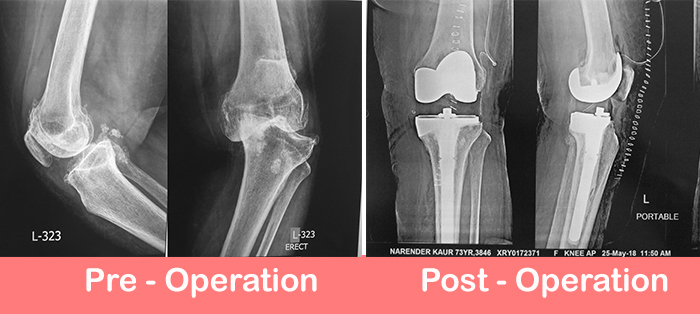

73 years old lady suffering from osteoarthritis of both knees came to us with pain and deformity both knees. She had severe varus and flexion deformity in left knee with large tibial defect.

Total knee replacement with unconstrained implant and stem wedge for tibial bone loss was done. Patient is recovering well and walking from next day of surgery.